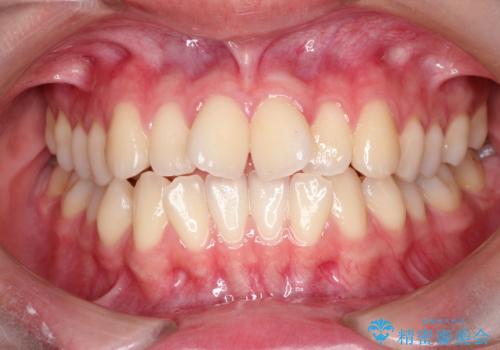

重度の不正咬合 Cl.Ⅱ div.2 を表のワイヤー矯正で綺麗に!

- 右下の第2小臼歯は完全に埋伏していたため、これは歯列に勘定せず計画をたてた

→右側は上顎第1小臼歯の抜歯によるCl.Ⅰ目標

→左側は上顎第1小臼歯抜歯・下顎第2小臼歯の抜歯によるCl.Ⅰ目標

一般的なCl.Ⅱ div.2の治療法に基づき、上顎のフレアアウト後に抜歯を行い、スペースクローズに移行した